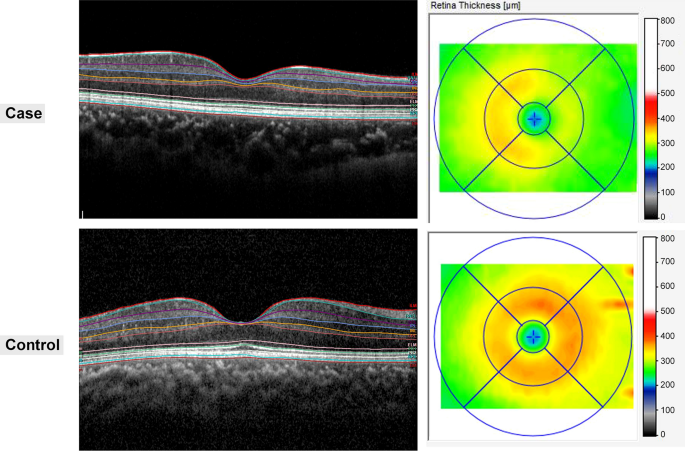

Two representative cases of patients diagnosed postoperatively with juvenile craniopharyngioma and healthy controls. B-scan of spectral-domain optical coherence tomography with auto-segmentation (in-built Spectralis mapping software, Heidelberg Eye Explorer HEYEX version 1.10.2.0) into the following retinal layers: RNFL retinal nerve fiber layer, GCL ganglion cell layer, IPL inner plexiform layer, INL inner nuclear layer, OPL outer plexiform layer, ONL outer nuclear layer, PRL photoreceptor layer.

Seven retinal layers were identified via automated segmentation using Spectralis software with manual correction as needed. The thickness of each layer between the vitreoretinal interface and the outer border of the retinal pigment epithelium was measured automatically. The whole retinal layer was segmented into seven respective retinal layers: the RNFL, the GCL, the IPL, the INL, the OPL, the ONL, and the PRL. Following the automated segmentation of each retinal layer, the thickness of each retinal layer in the 3- and 6-mm subfields as defined by the ETDRS grid was automatically measured using the Spectralis mapping software (Fig. 2). The average thickness of the four macular quadrants measured within the 3 mm and 6 mm zones was calculated for each layer. The segmentation was based on a validated algorithm used to measure the average thickness values within a 3 × 3 mm circle and a 6 × 6 mm extended area centered at the fovea. The foveal region, consisting of a 1 × 1 mm circle, was excluded from the analysis. The quality of all images was reviewed by two independent graders (G.I.L. and K.A.P.). We manually corrected any errors in the automated segmentation, as reported previously by Oberwahrenbrock et al.34.